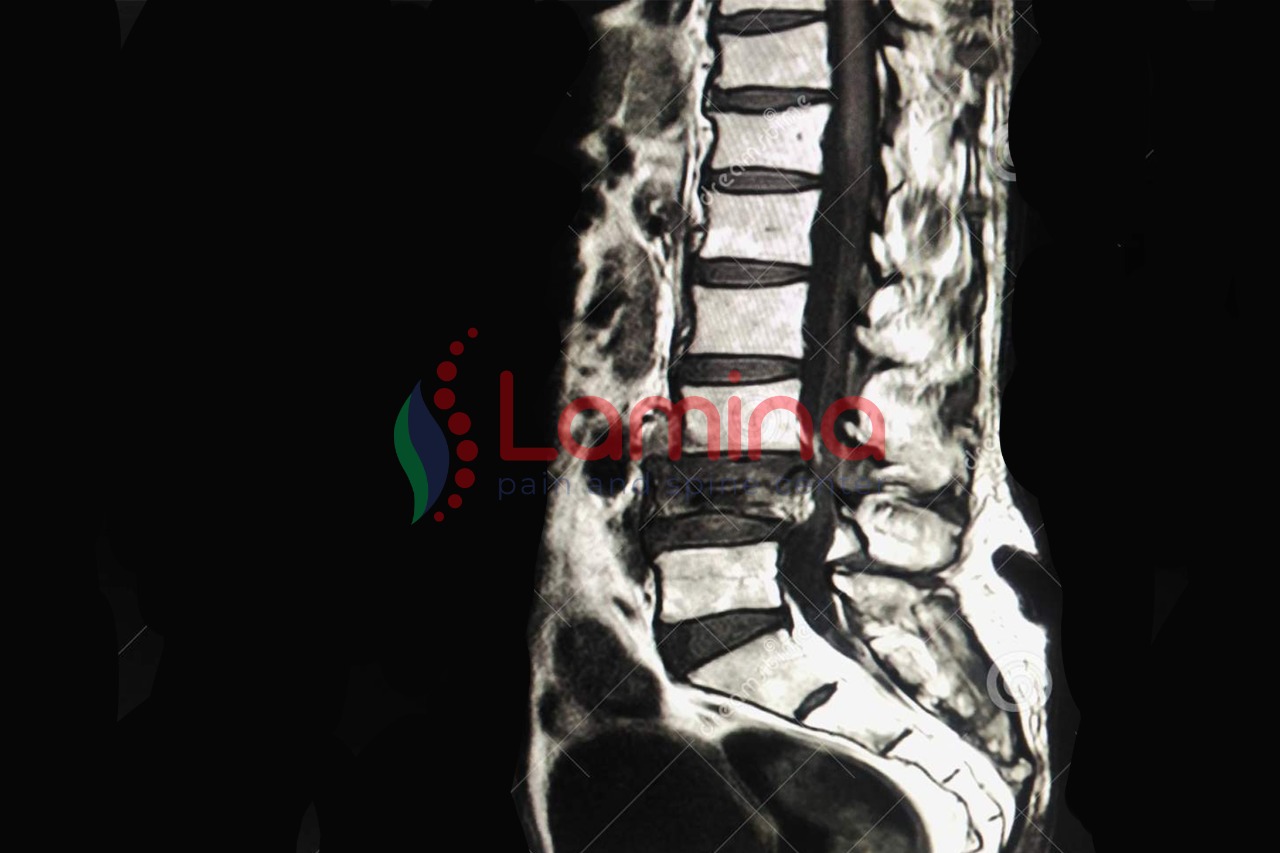

Nyeri pinggang bisa juga terjadi akibat saraf kejepit/ HNP. Penderita HNP akan mengalami gejala seperti nyeri hebat, rasa seperti terbakar, ngilu, kesemutan atau kebas di bagian tubuh tertentu, hingga nyeri yang menyengat seperti disetrum.

Dulu, untuk menanganinya perlu operasi. Namun, seiring meningkatnya teknologi kedokteran, saat ini terdapat metode terbaru HNP yang relatif cepat dan aman untuk terapi syaraf terjepit di Klinik Lamina yaitu dengan metode PELD (Percutaneous Endoskopi Lumbar Discectomy).